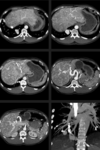

O melhor método de avaliação é a __ (TC/RM).

A

RM.

Perda do sinal do fígado em paciente com hemocromatose primária acentuada.

Na TC o achado de aumento da atenuação é inespecífico, encontrado também em diversas outras doenças (uso de amiodarona, sais de ouro, doença Wilson)

Vantagens da RM?

• Confirmação diagnóstica;

• Quantificação da sobrecarga férrica;

• Determinar severidade;

• Monitorar terapia;

• Diferenciar hemocromatose primária e secundária.

Graduação da sobrecarga férrica na RM.